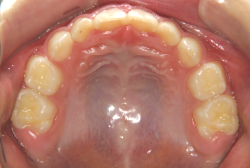

凸凹な歯並びのことを叢生といいます。矯正歯科に来院する患者様の主訴の中で、最も多いのが「配列の凸凹を真っ直ぐにしたい」というものです。歯の大きさと顎の大きさの調和がとれていないことが原因です。

凸凹を主体としたケースの場合、当院の平均治療期間は18ヶ月ですので、このケースは少し長めに経過しました。理由の一つは凸凹の程度がかなり重症だったと言うことですが、もう一つは、右下第2大臼歯が45度くらい前傾していたため、それを整直化させるために時間を要したと考えています。いずれにしても最終結果は大変よい状態と思います。

治療前は並びが乱れて見た目が悪いというのはもちろん問題ですが、歯科医学的に一番困るのは噛み合わせが悪いという点です。上下の犬歯(3番目の歯)は、上下的に離れた位置にあるため接触することができません。つまり歯としては存在していても、歯としては機能していないということです。